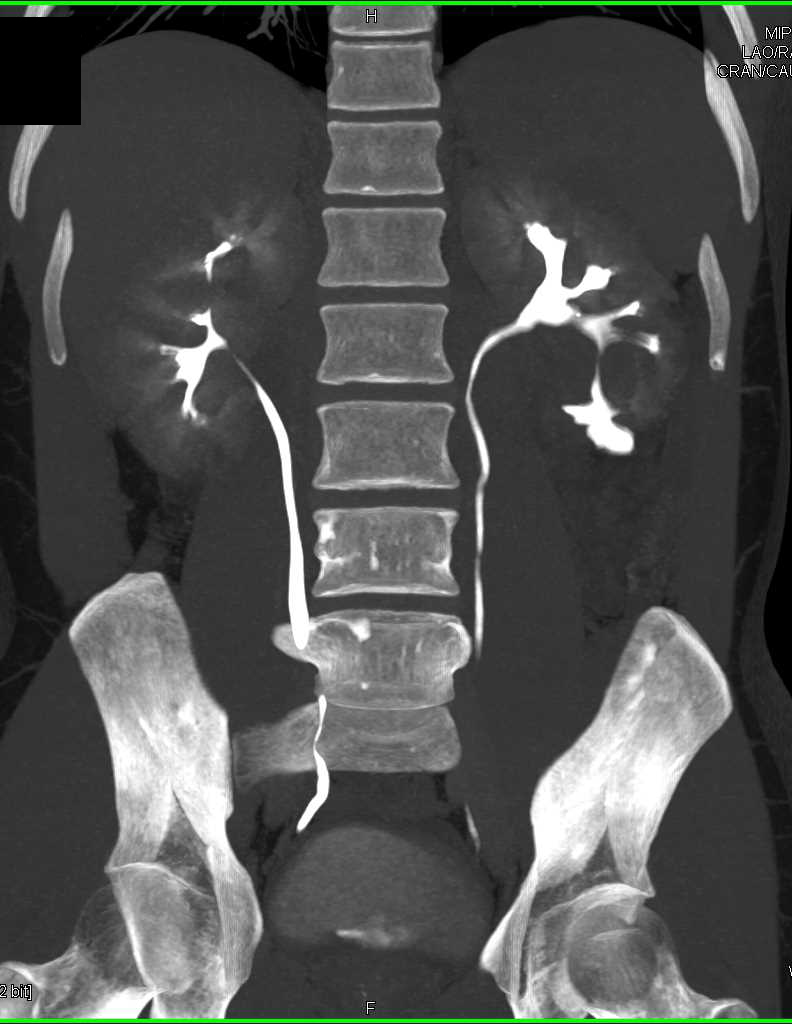

Metastatic Renal Cell Carcinoma to the Omentum and Liver